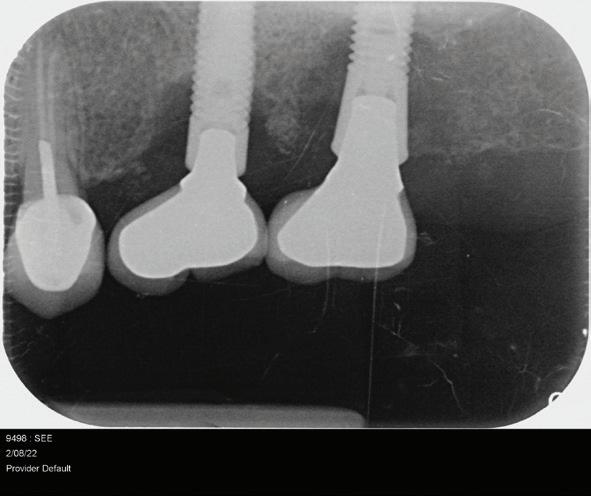

Figure 1: Radiographic Image of implants do not demonstrate bone loss due to the bisecting angle of the radiograph taken.

Figure 2: Radiographic image in a paralleling technique of implants dem onstrate moderate peri-implantitis with bone loss that will necessitate treatment.